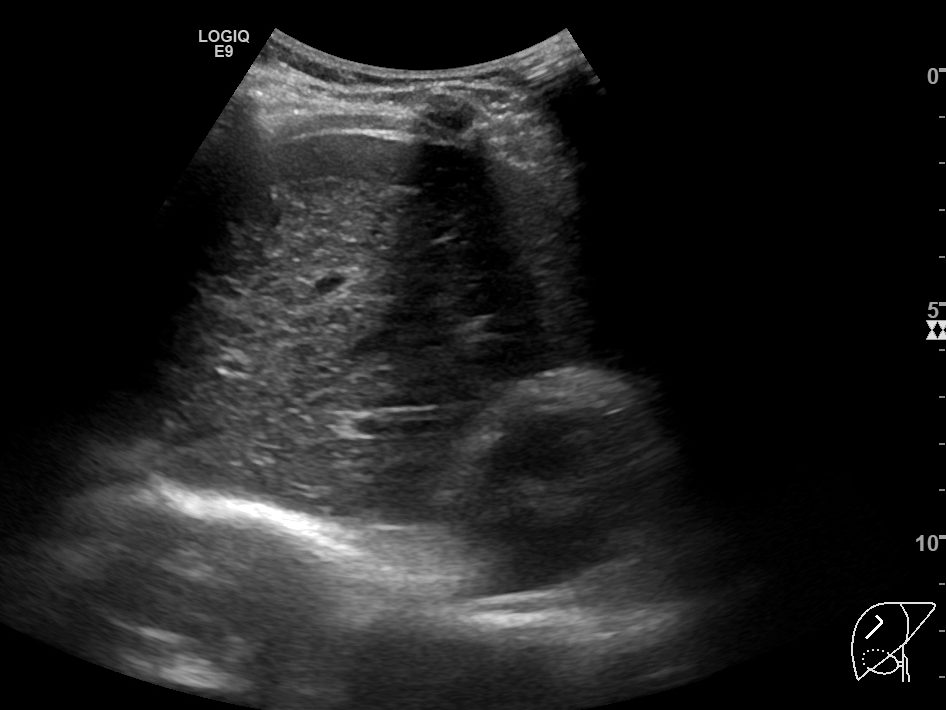

위의 두 영상은 간초음파에서 우간정맥(Rt. hepatic vein)의 장축을 따라 얻은 B모드 및 컬러도플러 영상입니다. 간실질 에코가 매우 거칠고 불균일한 만성 간질환 환자인데, 도플러영상에서 장축 전체에 걸쳐 뚜렷하게 확인할 수 있는 우간정맥이 B모드영상에서는 희미하게 일부분만 보입니다. 심지어 확인되는 부분도 컬러 도플러영상에서 보이는 것보다 훨씬 가늘어보이죠.

반면, 혈류가 반대방향이어서 빨갛게 보이는 간문맥(Rt. portal vein)의 경우는 B모드 영상에서도 간문맥 벽이 뚜렷하게 보일 뿐 아니라, 굵기도 컬러도플러 영상에서 확인되는 것과 별로 큰 차이가 나지 않습니다.

간초음파를 시행하면서 확인해야 하는 표준영상 중에는 우간정맥의 장축을 포함하는 영상이 포함되어있습니다. 마찬가지로 간좌엽의 시상면영상을 확인할 때에도 좌간정맥(Lt. hepatic vein)이 포함되어 촬영하는 게 보통입니다. 그렇게 간정맥을 확인하는 과정에서 위와 같이 간정맥이 잘 보이지도 않고, 실제 직경보다 훨씬 작게 보이는 이런 현상은 현장에서는 굉장히 흔한 현상입니다.

B모드영상에서 간정맥이 실제보다 훨씬 얇고 희미하게 보이거나, 아예 잘 보이지 않는 이유는 간정맥의 혈관벽이 얇아서 초음파신호가 반사되지 않아 영상에서 혈관벽을 특정할 수 없기 때문입니다. 특히 간실질의 에코음영이 거칠거나 간섬유화가 심하게 진행된 만성 간질환 환자들에서 간정맥을 확인하지 못하거나, 굉장히 가늘게 보이는 경우가 많습니다.